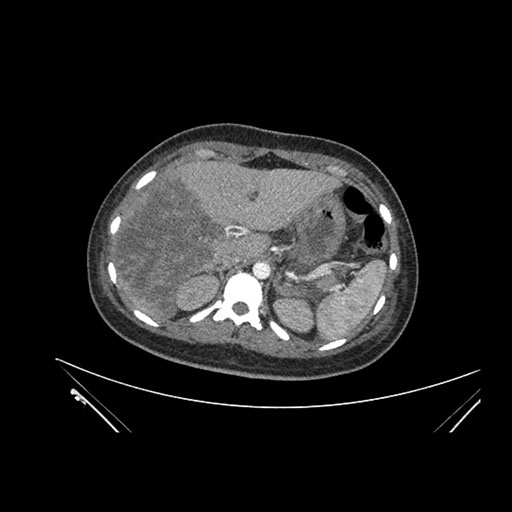

Axial Arterial